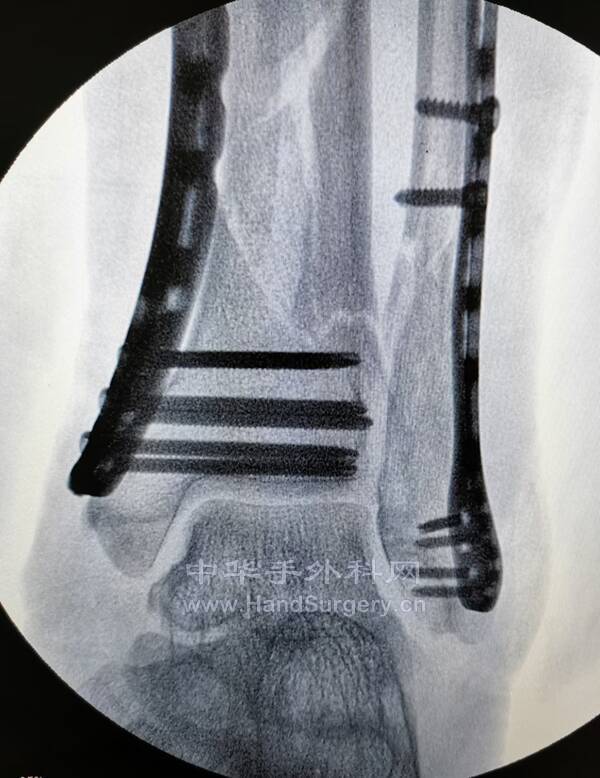

桡骨远端骨折,远端粉碎或太短,不能接受钢板远端钉排

克氏针+外固定支架是绝佳选择

这里就是其中一个典型病例

桡骨远端骨折C3型合并舟骨骨折

有限切开,外固定架的持续牵引,可以利用软组织夹板作用,维持粉碎骨块的复位